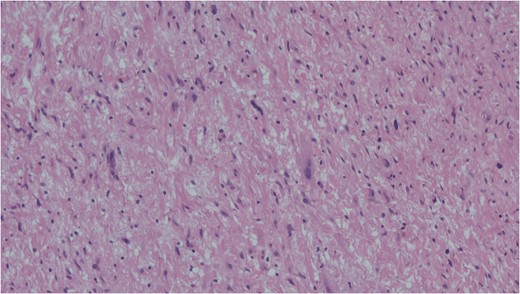

Cells with enlarged hyperchromatic nuclei seen in ancient schwannoma. Haemotoxylin and eosin (H&E).

FNAC remains a valuable tool to characterize neck masses but its accuracy in schwannoma is only reported to be 20–25% [4, 6]. Macroscopically, schwannomas are smooth and uniform and often attached to their nerve of origin which may help intra-operative diagnosis. Histologically, schwannomas are encapsulated and consist of alternating Antoni-A and Antoni-B regions [7]. Ancient schwannomas can be recognized by their additional degenerative features such as fibrosis, cystic necrosis and degenerative nuclei [7]. They can often be mistaken for malignant tumours due to nuclear atypia and hyperchromasia [7].